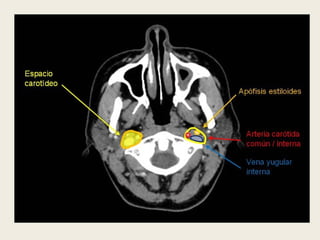

ESPACIO CAROTÍDEO (O ESPACIO

Las 3 capas de la fascia cervical profunda

contribuyen a la formación de la vaina que

circunscribe este espacio, que se extiende desde

la base del cráneo hasta el arco aórtico. Su

porción suprahioidea contiene la arteria carótida

interna, la vena yugular interna, ganglios

linfáticos, los pares craneales del IX, X y XI y el

plexo simpático cervical.

ESPACIO CAROTÍDEO

 Está rodeado por una

vaina, en la que

participan las 3 capas

de la fascia cervical

profunda.

 Contiene la vena

yugular, las carótidas

común e interna y el

nervio vago. El plexo

simpático cervical y

numerosos ganglios

linfáticos están

englobados en la

pared medial de la

vaina.